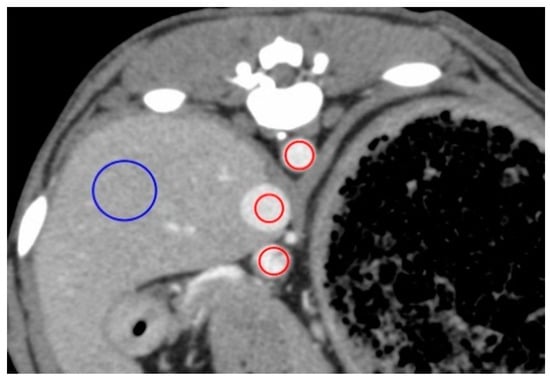

With regard to time-based parameters, in four dogs under the sedation protocol, CVC enhancement occurred earlier than AO enhancement, with a strong peak of CVC enhancement (Figure 5). We noted that in one dog in the sedation protocol, an early strong CVC enhancement was not observed, with a CVC-EA value of 50 s, CVC-EP value of 74 s, and a peak enhancement value of 154 HU (Table 1). Not only was the contrast enhancement earlier with the sedation than the anesthesia protocol (namely, CVC-EA and CVC-EP) in this animal, but also the peak enhancement value of CVC (CVC-EP) reached a maximum under the sedation protocol. All dogs fully recovered from anesthesia and sedation.

With sedation, except in one dog, contrast enhancement of the CVC appeared earlier than the effect in the AO. Moreover, contrast enhancement values of the CVC were the highest among all measured contrast enhancement values, with this state persisting for at least 40 s after the administration of contrast medium. This finding is indicative of a sedation-induced bradycardia and a weakened cardiac output; therefore, the contrast medium may have stagnated in the CVC without entering the pulmonary circulation. In humans, this characteristic effect is known as the “inferior vena cava level contrast” or “dependent pooling sign” and is observed clinically in patients who are in shock due to cardiac arrest, cardiac tamponade, or myocardial infarction [28,29,30]. This effect, in humans, results from the contrast medium permeating into the CVC from the right atrium due to reduced cardiac output and blood pressure. However, all dogs in our study did not exhibit hypotension under sedation. Hence, the CVC effect observed was likely due to a reduced cardiac output secondary to both, bradycardia and an increase in afterload.

Figure 5. Image obtained 11 s after injection of the contrast medium in one representative dog under the sedation protocol, showing a strong CVC enhancement, with no contrast in the AO and PV. AO, aorta; CVC, caudal vena cava; PV, portal vein.